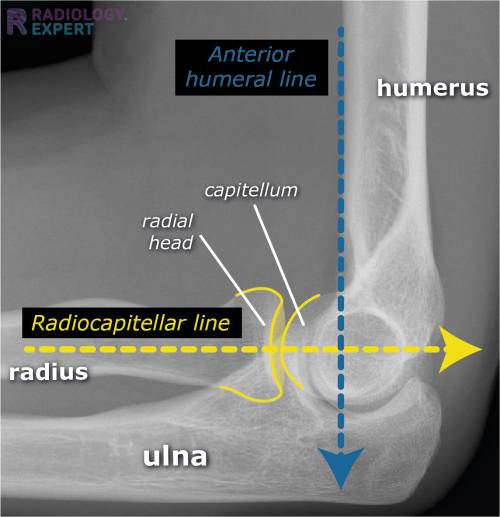

humeral line anterior elbow supracondylar pediatric fractures normal radiology fracture humerus radiopaedia capitellum angle capitulum joint case types injuries occult

elbow ray radial fracture head normal alignment line anterior humeral coreem

elbow forearm normal lateral alignment anterior capitellum radiograph interpreting radiographs fracture supracondylar intersect

elbow line anterior normal radiocapitellar humeral fractures adults lateral radiograph dislocations imaging

humeral radiocapitellar elbow radiographic

elbow humeral fracture supracondylar forearm capitellum radiographs interpreting intersect

elbow xrays humeral radiocapitellar emdocs fracture

elbow xrays anterior humeral radiocapitellar emdocs fracture

humeral lateral elbow rogers

radiopaedia line humeral anterior radiology

capitellum dislocation elbow pediatric through drawn lateral anterior humeral pass should line